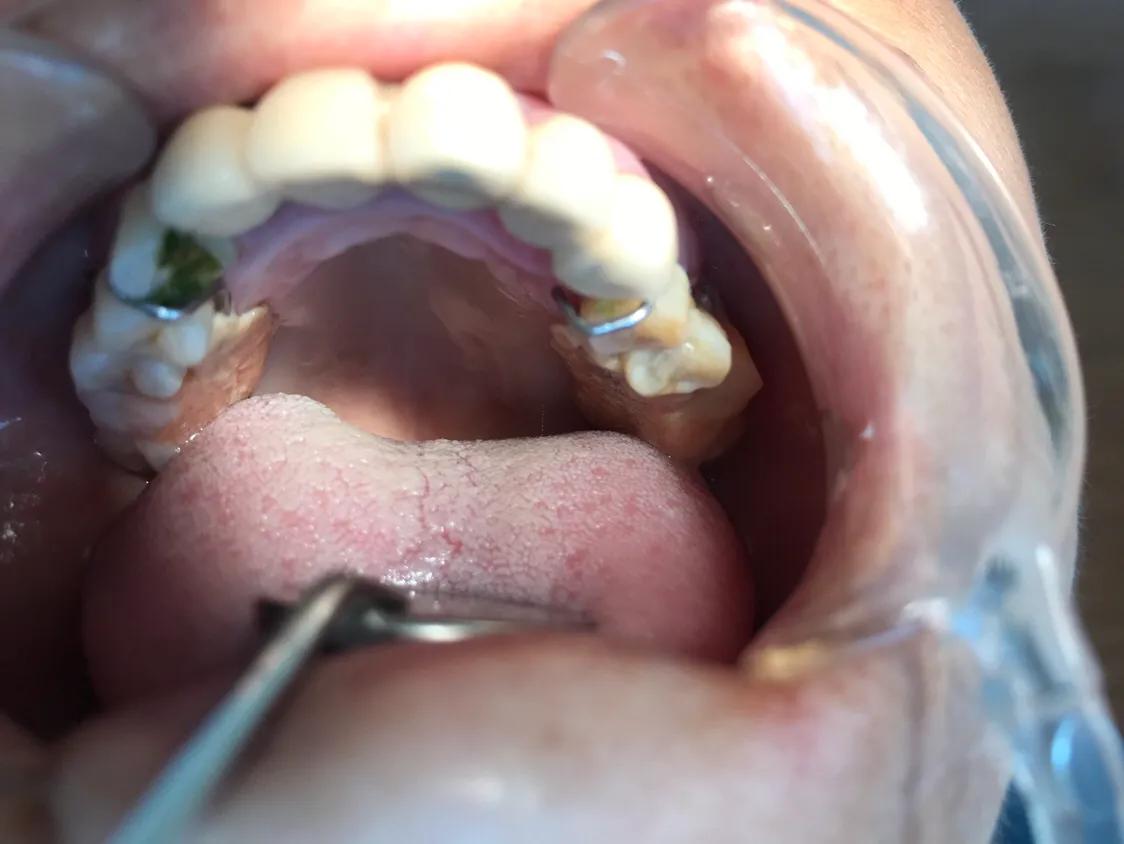

3.不良修复体

早些年,江湖游医在一些偏远地区,尤其是农村里,做一些假牙。正规的活动假牙是可以自己摘戴清洗,而这些不良的修复体,自己摘不下来,大量食物残渣聚集,却不能清洗干净,导致很多问题。

不良修复体的处理方法 拆除

未按规定处理将面临的处罚 蛀牙未处理的一起严重后果,牙龈出血,口腔溃疡,不能做磁共振检查,有的甚至出现口腔癌等可怕后果。